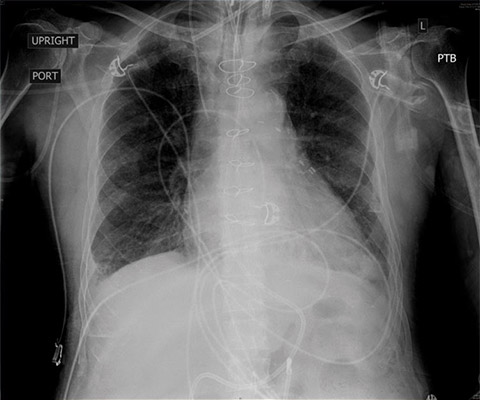

Given his renal failure and anticipated limitations to aggressive diuresis with medical therapy, arrangements were made to emergently intubate the patient, augment ionotropic support, escalate diuresis attempts with diuretics while calling the family to discuss care options including likely need for dialysis. As the patient was being prepped for intubation, X-ray imaging was obtained confirming the diagnosis of pulmonary edema. By then, though, the patient had already been given aggressive diuretic therapy, received escalating ionotropic support, bronchoscopy was set up at the bedside for endobronchial evaluation after the intubation given his fevers, and the family had been notified. POCUS with a small, extremely portable device had allowed for convenient and rapid evaluation, diagnosis, and intervention in a complex patient. A repeat chest X-ray just one hour after intubation showed marked improvement in the patient’s pulmonary edema.Clinical impact

CXR pre-intubation showing diffuse bilateral alveolar and interstitial pulmonary edema.

CXR one-hour status post intubation, after initiation of aggressive diuresis, augmentation of ionotropic support, and positive pressure ventilation.